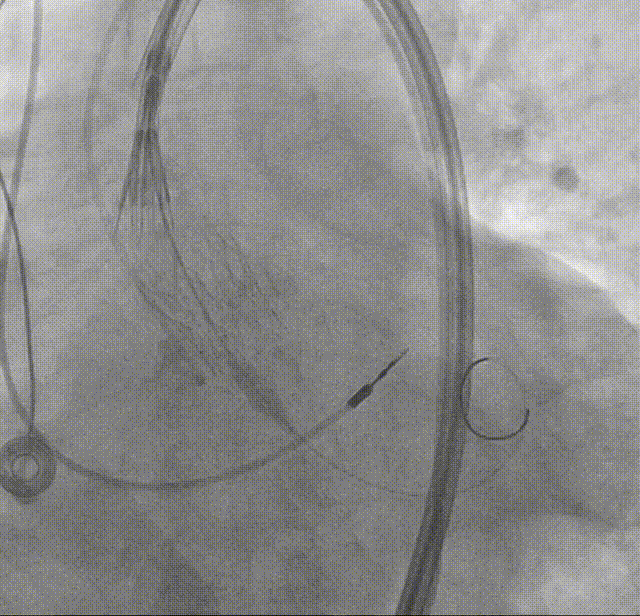

打平瓣架后造影评估:瓣架形态佳,植入位置可(接近0位),可见瓣周漏,冠脉显影可

考虑瓣膜形态与位置均可,备球囊后扩处理方案,决定进行瓣膜脱钩,可见瓣膜脱钩稳定无位移

回收挂钩